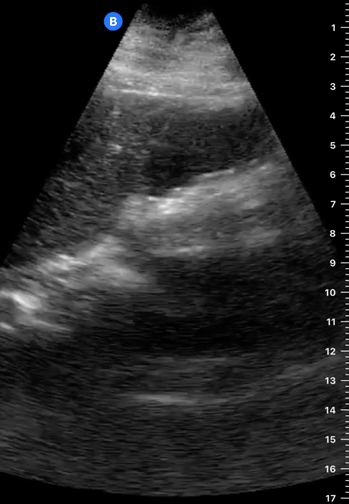

Classically, GB calculi are described as intraluminal hyperechoic images that cast posterior acoustic shadows. If not impacted, they should also be mobile and have gravitational dependence. Consequently, scanning the patient in more than one position may elucidate an impacted gallstone, as it will not move with gravity. Neither a very small stone (<5 mm diameter) nor sludge will cast a posterior shadow, although multiple small calculi (microlithiasis) may present poorly defined shadowing.

WALL ECHO SHADOW

If the gallbladder is completely filled with stones, the normal fluid-filled structure with posterior enhancement is no longer seen. Instead, the wall echo shadow (WES) sign can be found as two parallel bright lines with a large posterior shadowing. The bright line closest to the probe is the GB wall and the line beneath represents the echogenic calculi. WES is important because it may be misinterpreted as a bowel loop, when in fact represents cholelithiasis.

Be mindful that not every echogenic image inside the GB lumen is a stone. Neither gallbladder polyps nor sludge will cast acoustic shadowing, the latter, however, has gravitational dependence, while polyps do not move when repositioning the patient.